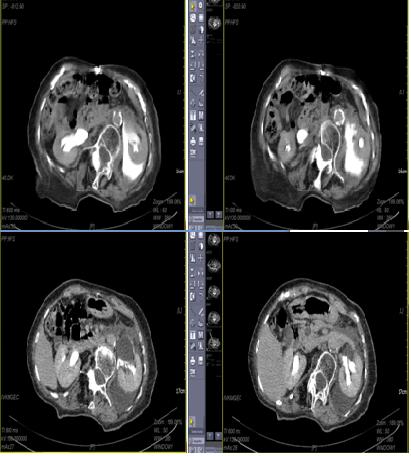

OLGU: 86 yaşında bir kadın hasta acil kliniğine son 7 gündür devam eden sol yan ağrısı ile başvurdu. Hastanın bir ay önce tanı almış sol böbrek taşı olduğu ve tedavi olarak hidrasyon ve analjezik aldığı öğrenildi. Ağrı son 24 saatte artmış ve hastada bulantı, kusma ve karnın sol tarafında hassasiyet gelişmiş. Yapılan USG’de sol hidronefroz ve sol perinefrik alanda abondan sıvı koleksiyonu görüldü, sağ böbrek normaldi. Sonrasında İV kontrastlı abdominopelvik tomografi çekildi; UPB’de 8 mm taş, sol perinefrik sıvı koleksiyonu, kontrast ekstravazasyonu görüldü ve sol renal pelvis rüptürü tanısı kondu (Şekil 1). Tetkiklerinde lökosit düzeyi 14.900, üre ve kreatinin normaldi. Ağrı kontrolünün ardından hastaya floroskopi altında sol DJ tatbiki uygulandı. Operasyonun ardından hastanın genel durumu birkaç saat içinde daramatik olarak düzeldi. Postoperatif 3.günde hastaya kontrol tomografi çekildi. Perinefrik alan öncekinden daha temiz izlendi ve sıvı koleksiyon azalmıştı. Taburculuk sonrası postoperatif birinci ayda hastaya bir seans SWL uygulandı, hasta taşsız hale geldi. SWL sonrası 2. haftada DJ stent çekildi.

CASE: An eighty-six year old woman has been admitted to emergency department with flank pain for last seven days. She had a UPJ stone for a month and hydration and daily oral analgesic were recommended to the patient. The pain increased in the last 24 hours, and patient has nausea, vomiting and tenderness in the left abdomen. Left hydronephrosis and abundant fluid collection in perinephric area were seen in ultrasonography. Then computerized tomography was performed and rupture of renal pelvis, perinephric fluid accumulation, contrast extravasation, and a 8 mm stone in UPJ were seen. Leukocyte level was 14900. Creatinine and urea were normal. After pain control, D-J stent was inserted under-fluoroscopy. After the operation patient’s clinical status was dramatically improved in a few hours. In control CT at postoperative third day, the perinephric area was clear and fluid collection was decreased. One session SWL was performed at postoperative 1st month. After the SWL patient become stone free. D-J stent was taken out after 2 weeks.

Şekil 1: BT görüntüsü

Figure 1: CT image